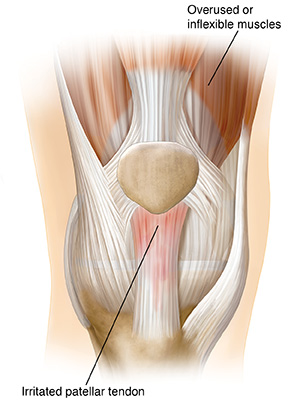

Patellar tendonitis

Patellar tendonitis (“jumper’s knee”) happens when the quadriceps muscles are overused or tight. During movement, the patellar tendon absorbs more shock than usual. The tendon becomes irritated or damaged.